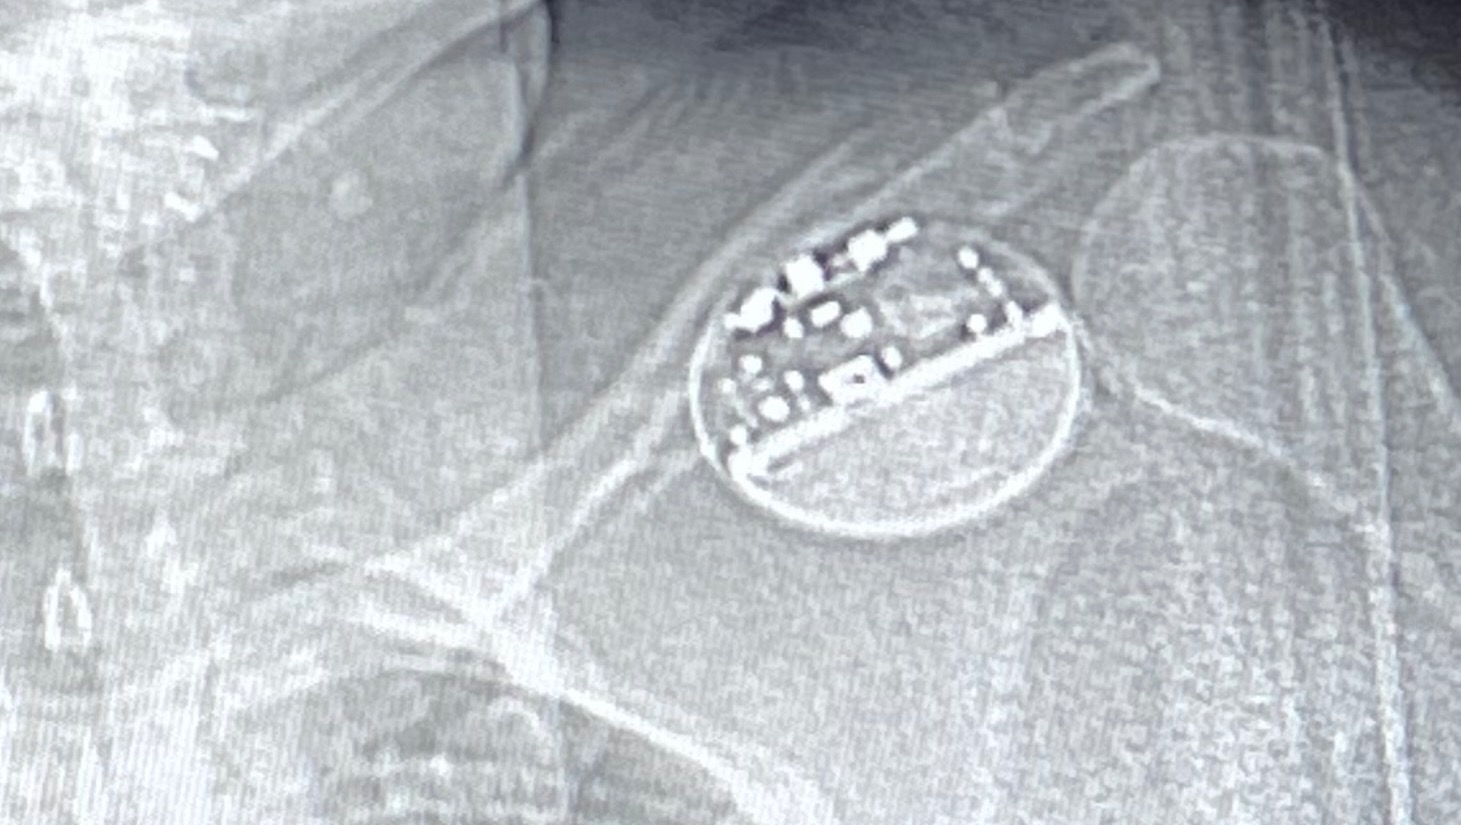

Update: Rori’s surgery didn’t go completely as planned, but they were able to install the device just not able to turn it on and get it going yet. So now in two weeks we will be going back for a second surgery. Not what we had hoped for but at least she is alright in the meantime. A set back for sure but she at least at home taking it slow at recovering a bit until the next surgery.

Over the last 10 + years Rori has developed Myoclonic and Tonic clonic seizures. They have rapidly increased and affect all of her daily life. Her last 43 hour brain scan (EEG) showed over 150 seizures. Over the last 2 years the seizures and the medication side effects got so bad she had to stop her business. Some days she has problems forming basic sentences, cooking, and even basic chores. Nathan is trying as hard as he can to continue to support their family while driving Rori to all the doctors appointments from eastern Washington to UW medical in western Washington for doctors, all shopping pretty much everything that needs to be done. This coming week, Rori will be going in for a surgery that is like a pace maker for her brain that will send a pulse through her brain to help send shock waves to hopefully help her have less seizures. Between this and the 4 medications she takes, she hopes to regain somewhat of a normal life for a bit. After surgery, every 1.5 to 2 weeks Nathan will need to take the day off, take Rori to the doctor to have the device calibrated for the next 6 plus months. Between this and missing work, and the 200 miles round trip it’s going to add up. The surgery bill, the hospital stay, the hotel stay for Nathan, and much more is all beginning to add up and weighing on Nathan’s shoulders as he tries to care for his wife.